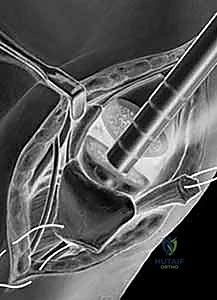

1. استئصال العظم المربعي مع إعادة بناء الأربطة (Trapeziectomy with LRTI)

تُعد هذه العملية "المعيار الذهبي" (Gold Standard) والأكثر شيوعاً ونجاحاً عالمياً لعلاج هذه الحالة.

• آلية العملية: يقوم الجراح بإزالة "العظم المربعي" (Trapezium) بالكامل، وهو العظم الذي يسبب الاحتكاك المؤلم. بمجرد إزالته، يختفي الألم تماماً لأنه لم يعد هناك عظم يحتك بعظم.

• **إعادة بناء الأربطة (LRTI):